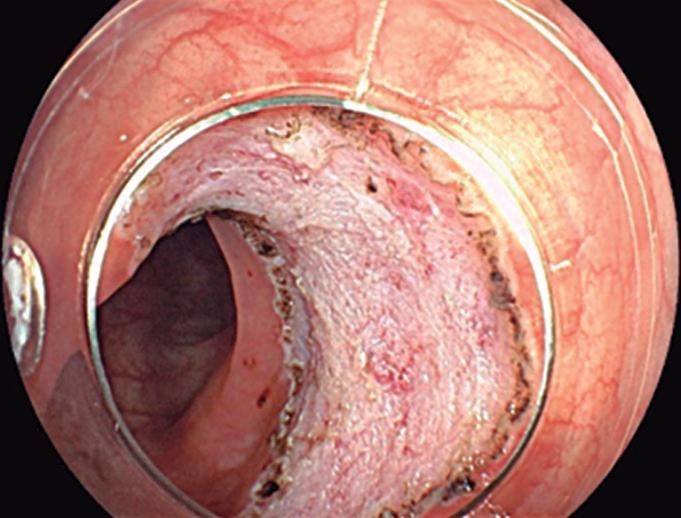

Evaluación endoscópica e histológica

La endoscopía superior es un procedimiento fundamental para el diagnóstico, la evaluación de la respuesta al tratamiento y el monitoreo a largo plazo de la actividad de la EEo. Los hallazgos endoscópicos típicos incluyen edema (reducción de vascularidad), anillos esofágicos fijos, exudados blancos, surcos longitudinales, estenosis, estrechamiento de la luz esofágica, friabilidad de la mucosa (mucosa en papel crepé) y una consistencia firme de la mucosa al realizar biopsias (signo de “tracción" o "resistencia”) en pacientes con fibrosis (Figura 1). Estos hallazgos no son patognomónicos y no constituyen un criterio diagnóstico; sin embargo, cuando se evalúa de forma cuidadosa, en la gran mayoría de los casos se pueden observar.19-21

En el panel A se observa un esófago con edema difuso y pliegues longitudinales; en el panel B se aprecia edema con pliegues y exudados blanquecinos; en el panel C se evidencia un estrechamiento luminal acompañado de anillos esofágicos y exudados; y en el panel D se muestra un desgarro mucoso posterior a la dilatación con bujía de Savary, hallazgo esperado tras este procedimiento terapéutico.

Figura 1. Características endoscópicas de la esofagitis eosinofílica